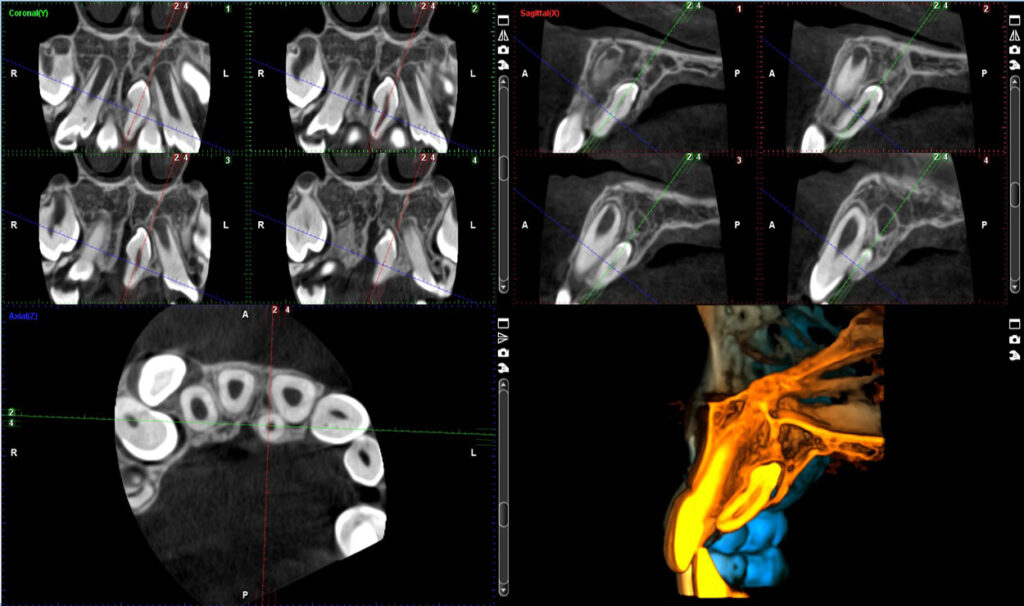

Primena CBCT snimka u oblasti endodoncije:

• Vizuelizacija impaktiranih zuba

• Procena položaja neizniklih zuba

• Identifikacija resorpcije korena

• Vizuelizacija prekobrojnih zuba

• Planiranje ortognatske hirurgije

• TMZ

• Vazdušni putevi

Malo polje Ø40×50 mm – Visoka rezolucija, veličina voxela 150 µm